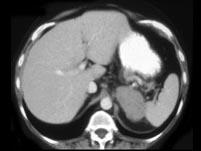

问题 女,47岁,满月脸、向心性肥胖伴高血压1月,请结合所提供图像,作出诊断 ( )

选项 A、左肾上腺嗜铬细胞瘤 B、左肾上腺增生 C、左肾上腺腺癌 D、左肾上腺转移瘤 E、左肾上腺腺瘤

答案 C